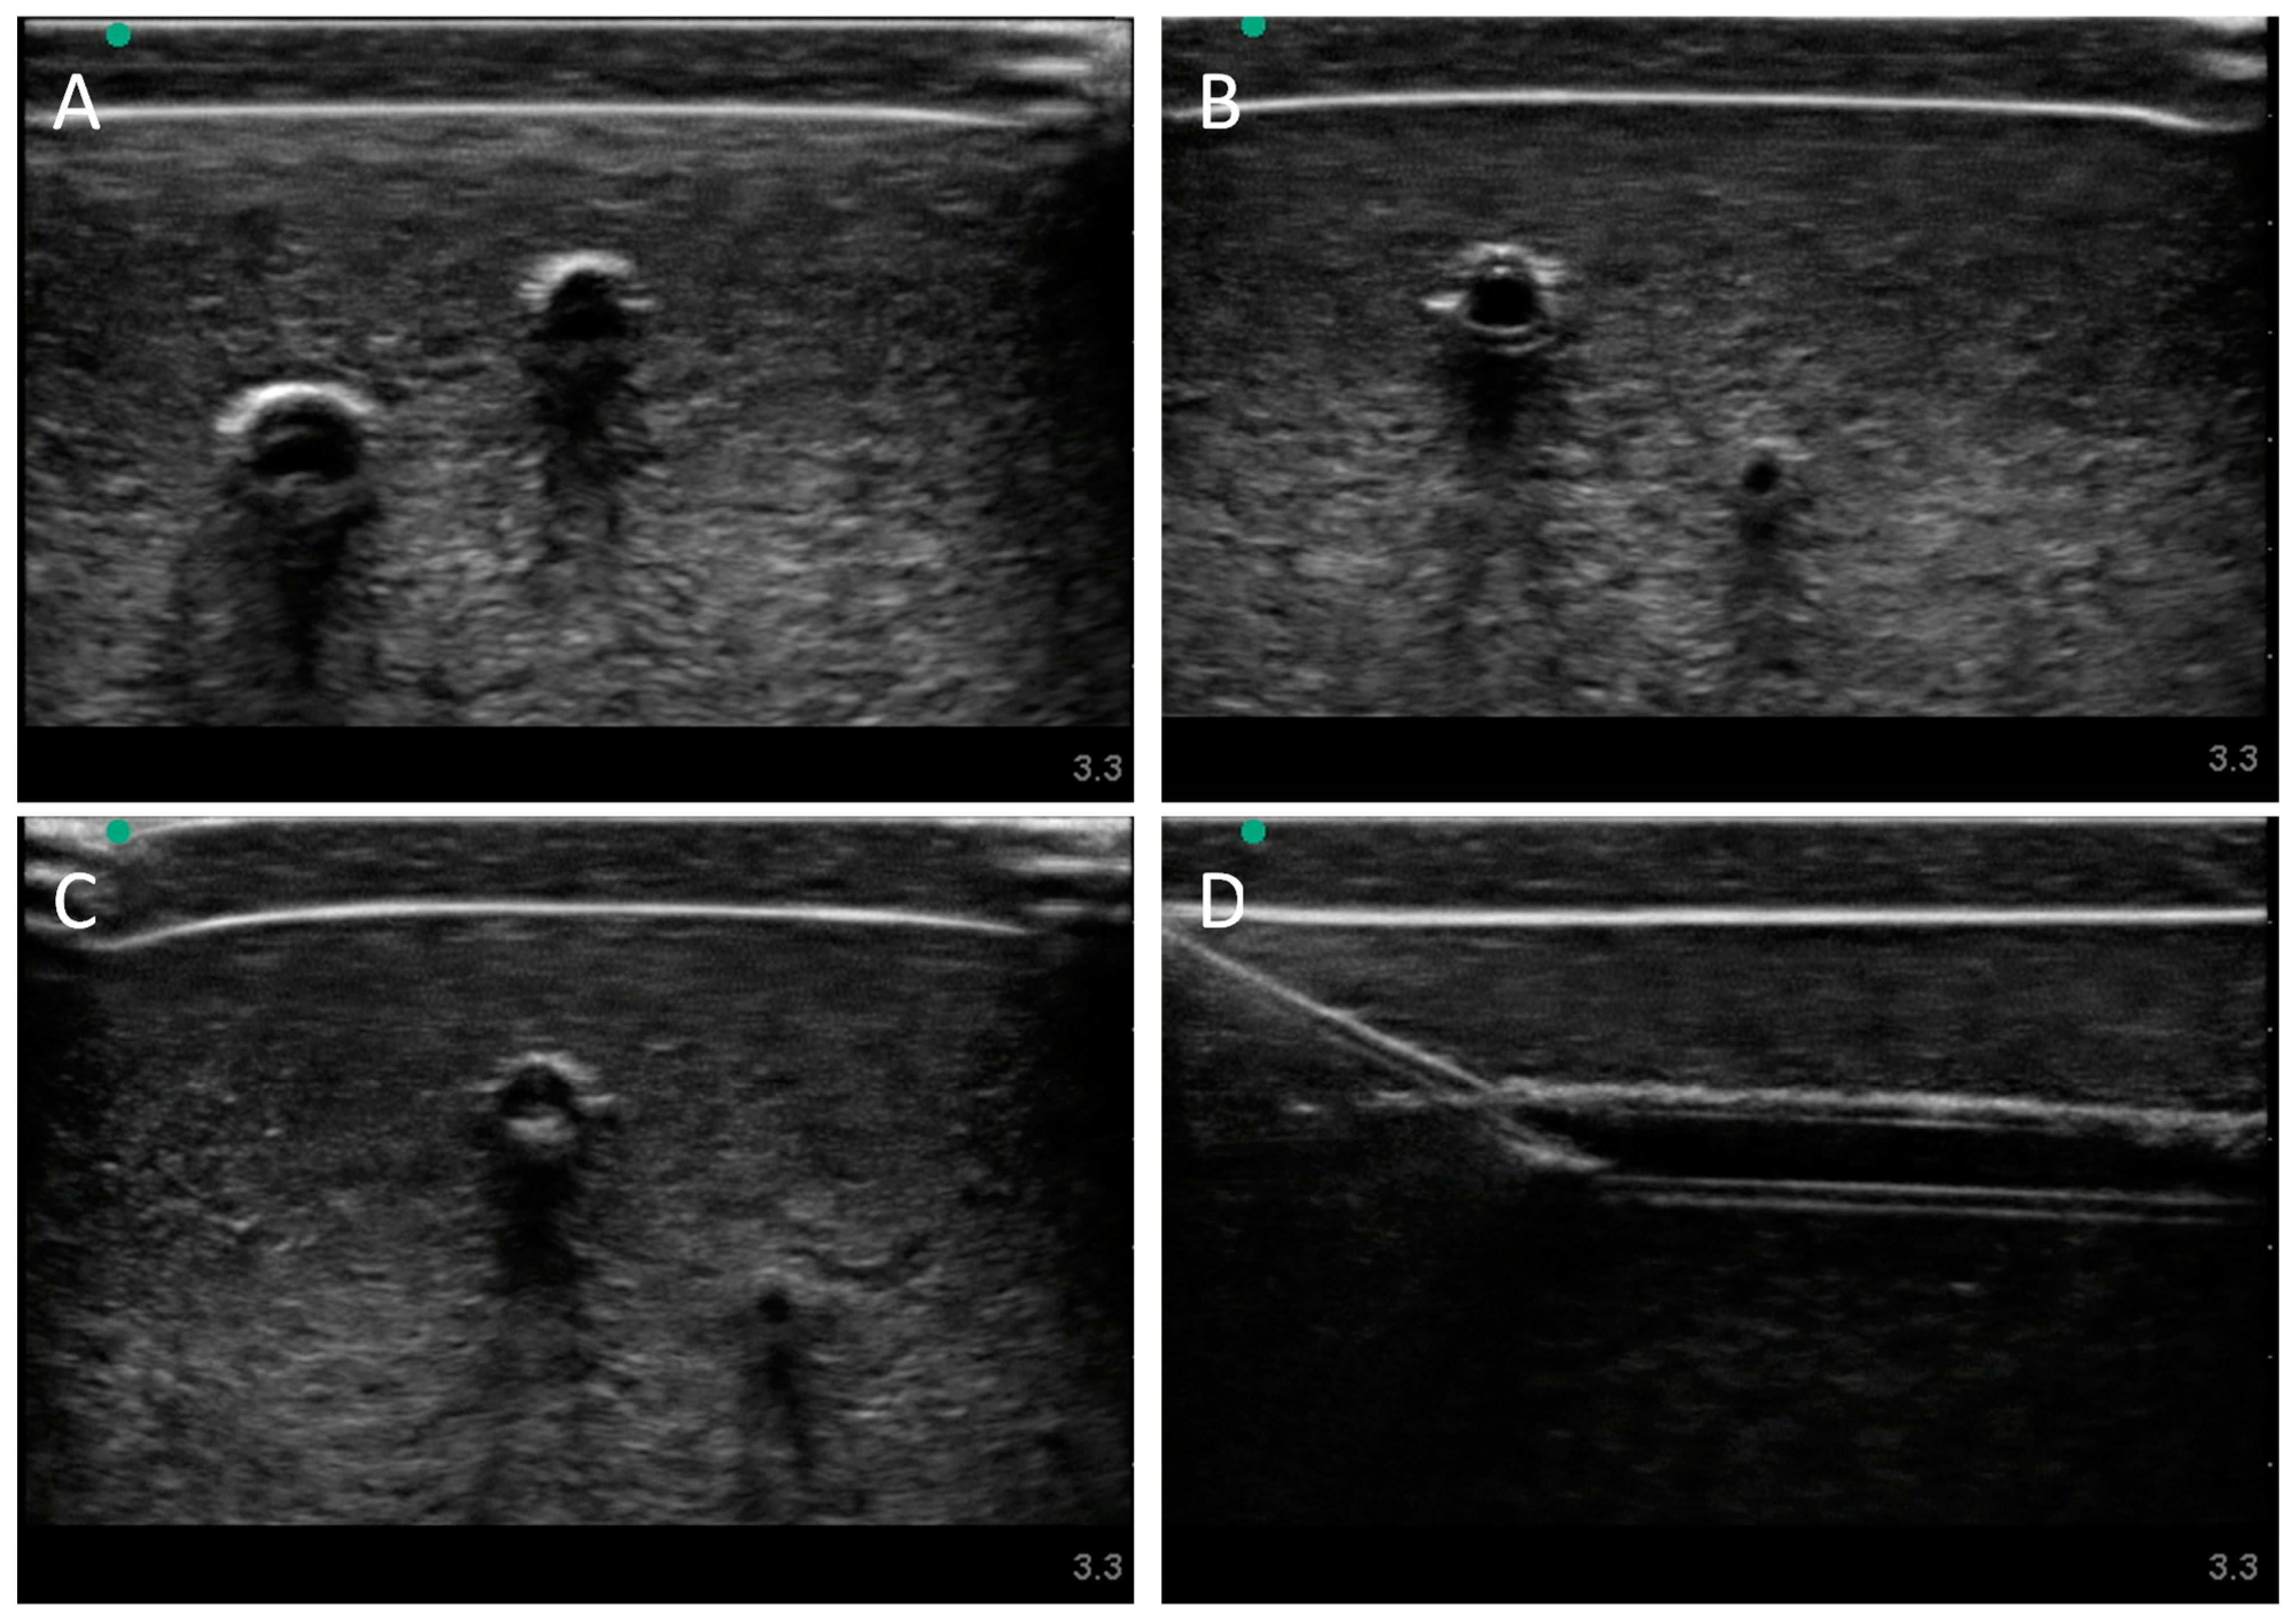

Next, we evaluated the swine phantom capability for ultrasound imaging. Latex tubing of various diameters was used to mimic veins and arteries within the tissue phantom and an external silicone layer was added to mimic skin. Overall, the gelatin phantom was ultrasound compliant, and the flour contained within the phantom bulk, as well as the evaporated milk fat, provided a hyperechoic ultrasound signal beyond the traditionally anechoic properties of gelatin hydrogels (Figure 4A). Needle insertion into the artery and vein was tracked in normal physiological conditions out of plane (Figure 4A artery, Figure 4B vein). As a result of the latex tubing used in the phantom, vessels were too rigid to collapse when mimicking hypovolemic levels just by reducing pressure in the system alone. Instead, smaller vessel sizes were integrated into the phantom with smaller latex tubing to mimic the reduced size of the artery and vein. Needle insertion could be tracked within hypovolemic levels for out of plane (Figure 4C artery) and in plane views (Figure 4D vein).

Figure 4. Porcine gelatin phantom ultrasound results. (A) Normovolemic OOP view of artery and vein, (B) hypovolemic OOP view of artery and vein, (C) hypovolemic OOP view with needle insertion into the artery with the needle tip visible close to lower vessel wall, and (D) hypovolemic IP view of needle insertion into the vein with needle bevel visible near the lower vessel wall.